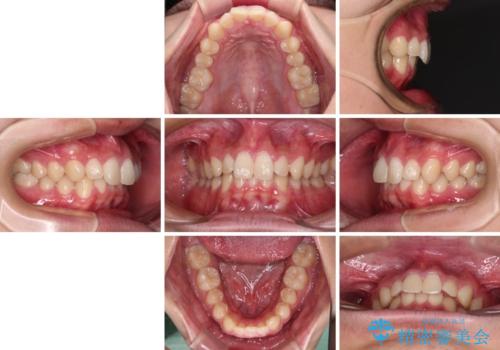

- 上下前歯のデコボコと深い咬み合わせを気にして来院された患者様です。

下顎前歯が一本欠損しており、下顎の歯列が小さいため、ディープバイトになりやすい状態でした。

ワイヤー矯正でもインビザライン矯正でも対応可能でしたが、インビザラインでの自己管理の煩わしさを避けるため、ワイヤー装置にて矯正治療を行うこととしました。